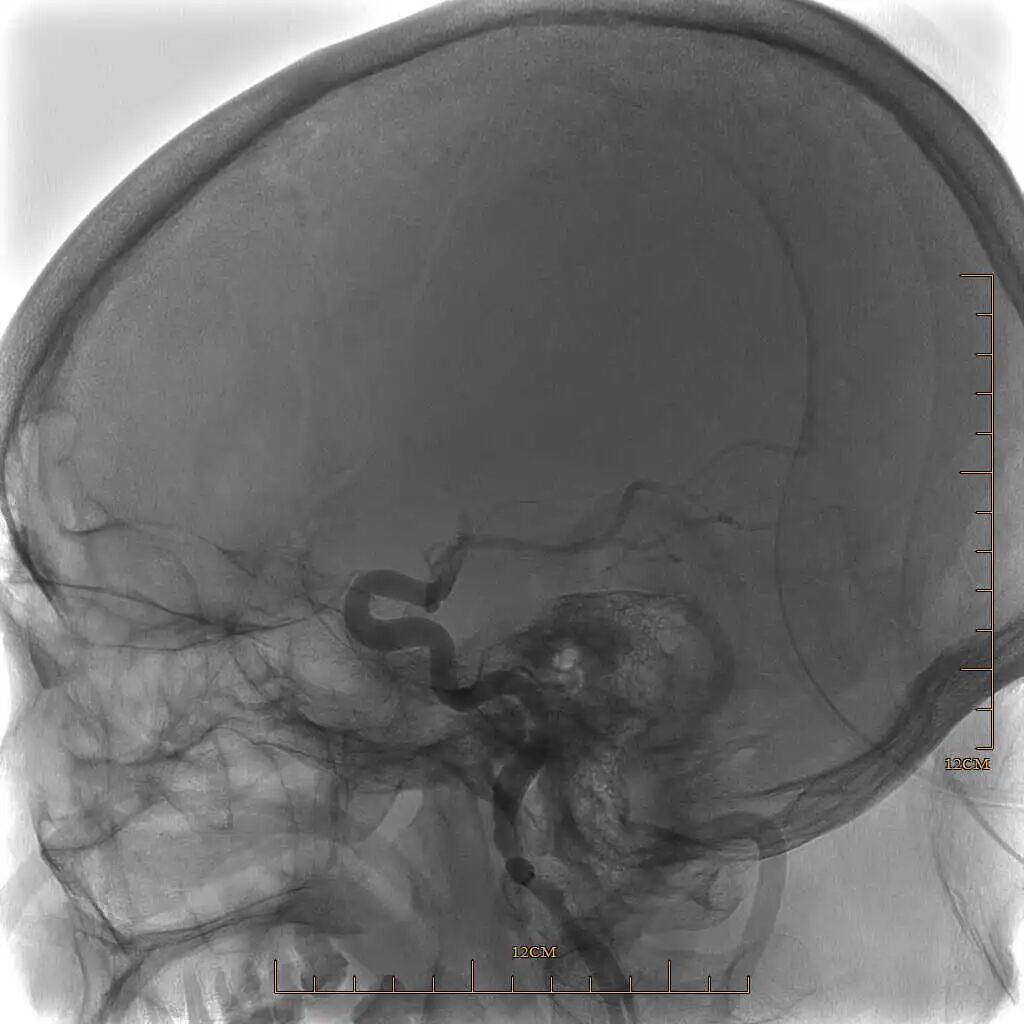

取栓后下干再通,上干仍闭塞。

动脉长鞘怎么置入有励可说|Locaste 088励楷长鞘及Tarvos微导丝在左侧大脑中动脉闭塞取栓术中的应用_https://www.jmylbn.com_新闻资讯_第13张

动脉长鞘怎么置入有励可说|Locaste 088励楷长鞘及Tarvos微导丝在左侧大脑中动脉闭塞取栓术中的应用_https://www.jmylbn.com_新闻资讯_第14张

Tarvos微导丝携微导管超选大脑中上干,微导管冒烟确认血管真腔,释放取栓支架。